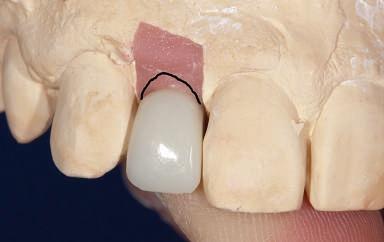

Figurile 3, 4. Întrucât poziţia implantului era mezială faţă de ideal, bonturile individualizate s-au conceput plate pe profilul mezial, dar au prezentat provocări în privinţa conturării restauratoare. 5. Restaurările implantare de la nivelul 1.2. şi 2.2. susţin o FPD metalo-ceramică cimentată între incisivii laterali.

Figurile 11-13. Deşi implantul s-a poziţionat la o profunzime normală în raport cu nivelul osului şi al ţesutului moale (fig. 11), va fi imposibilă crearea unei restaurări cu aceeaşi lungime ca dintele contralateral, din cauza plasării coronare a implantului (fig. 12). Restaurarea provizorie demonstrează discrepanţa lungimii dentare (fig. 13). 14. Un bont individualizat CAD/CAM. 15-16. Restaurare implantară la nivelul 1.1. Sondarea osului interproximal pentru a verifica plasarea adecvată a punctului de contact dinspre creasta proximală a osului, cu scopul de a asigura regenerarea completă a papilei interproximale (Fotografii cu amabilitatea lui Don Jayne, DDS). 17. Sunt evidente dificultăţile asociate unui bont standard pentru restaurarea dinţilor anteriori. Întrucât profilul bontului era insuficient, marginile au fost scurtate cu scopul de a lăsa spaţiu pentru conceperea profilului de emergenţă.